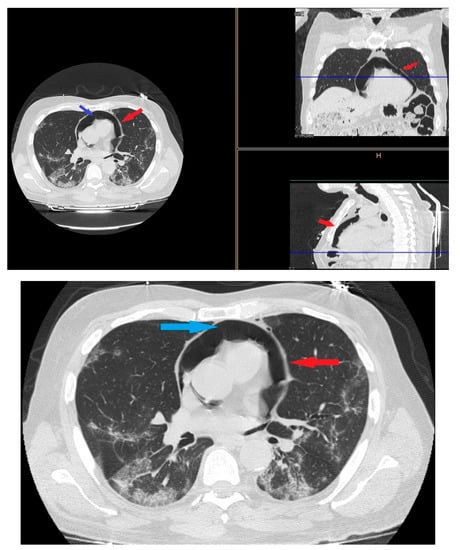

On day 12 computed tomography scan (CT) performed due to elevation of the dimer D at blood test revealed small layer of pneumomediastinum bubble with an increase in consolidation component without any clinician symptoms (Figure 3).

Figure 3. HRTC performed on day 12 showing pneumomediastinum bubble (red arrows) and increase in consolidation component (blue arrow). Detail of HRTC performed on day 12 with small layer of pneumomediastinum bubble.